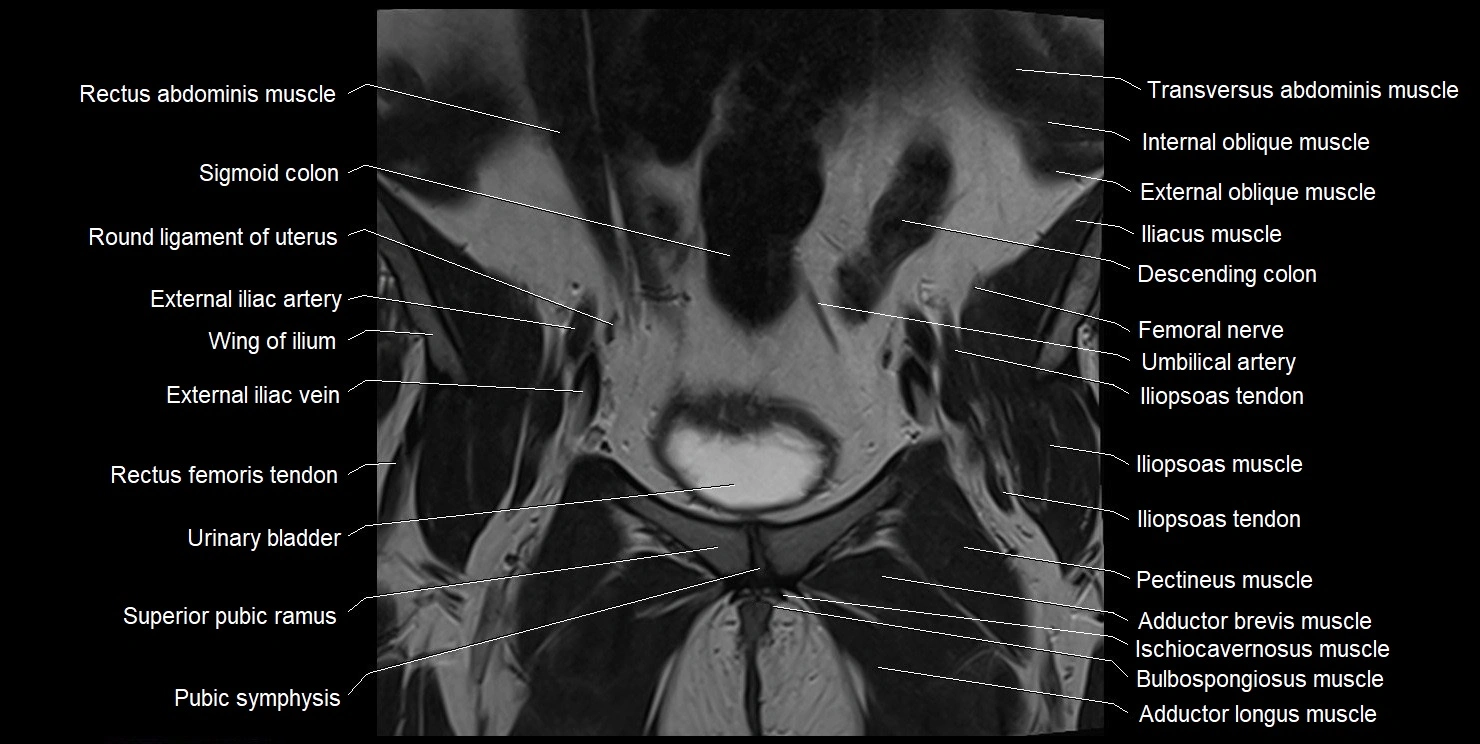

- Adductor brevis muscle

- Adductor longus muscle

- External iliac artery

- External iliac vein

- Femoral nerve

- Gracilis muscle

- Iliac crest

- Iliopsoas muscle

- Iliopsoas tendon

- Inguinal ligament

- Internal oblique muscle

- Linea alba

- Pectineus muscle

- Pubic bone

- Pubic symphysis

- Rectus femoris muscle

- Rectus femoris tendon (Proximal tendon of rectus femoris)

- Round ligament of uterus

- Sigmoid colon

- Superior pubic ramus

- Transversus abdominis muscle

- Umbilical artery

- Urinary bladder